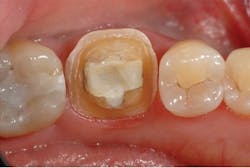

A 50-year-old female patient presented following a distobuccal fracture of tooth No. 19 (figure 2). After examination and discussion, a full-coverage restoration was planned. Local anesthesia was achieved with one cartridge of 4% Articadent Dental and epinephrine 1:100,000 (Dentsply Sirona). The tooth was carefully prepared to meet the reduction guidelines for Celtra Duo. In this case, a 1 mm circumferential shoulder was prepared with axial wall and occlusal reductions of 1.0–1.5 mm and 1.5 mm, respectively (figure 3).

Figure 2: Preoperative view of tooth No. 19 showing a distobuccal fracture necessitating a full-coverage restoration.

Figure 3: Final preparation of tooth No. 19.

The preparation design included a minimum of 1 mm reduction for a shoulder finish line, 1.0–1.5 mm reduction for the axial walls, and at least 1.5 mm reduction across the occlusal surface.